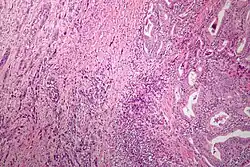

| Microscopic image of anaplastic thyroid carcinoma. H&E stain. | |

Anaplastic tumors have a high mitotic rate and frequently invades the local blood and lymphatic vessels.[5] Cellular death is frequently visualized on microscopic images.[2] The presence of regionally swollen lymph nodes in older patients in whom needle aspiration biopsy reveals characteristic vesicular appearance of the nuclei supports a diagnosis of anaplastic carcinoma. Microscopic images of ATC usually show inflammatory cells from the immune system such as T cells and macrophages.[2]

On immunohistochemistry testing, ATC is usually positive for the keratin, p53, and PAX8 proteins and is negative for thyroid transcription factor-1, thyroglobulin, and calcitonin.[2] ATC cells demonstrate high levels of PD-L1 expression.[2] BRAF and TERT mutations are seen more commonly in ATC than in differentiated thyroid cancer.[2]